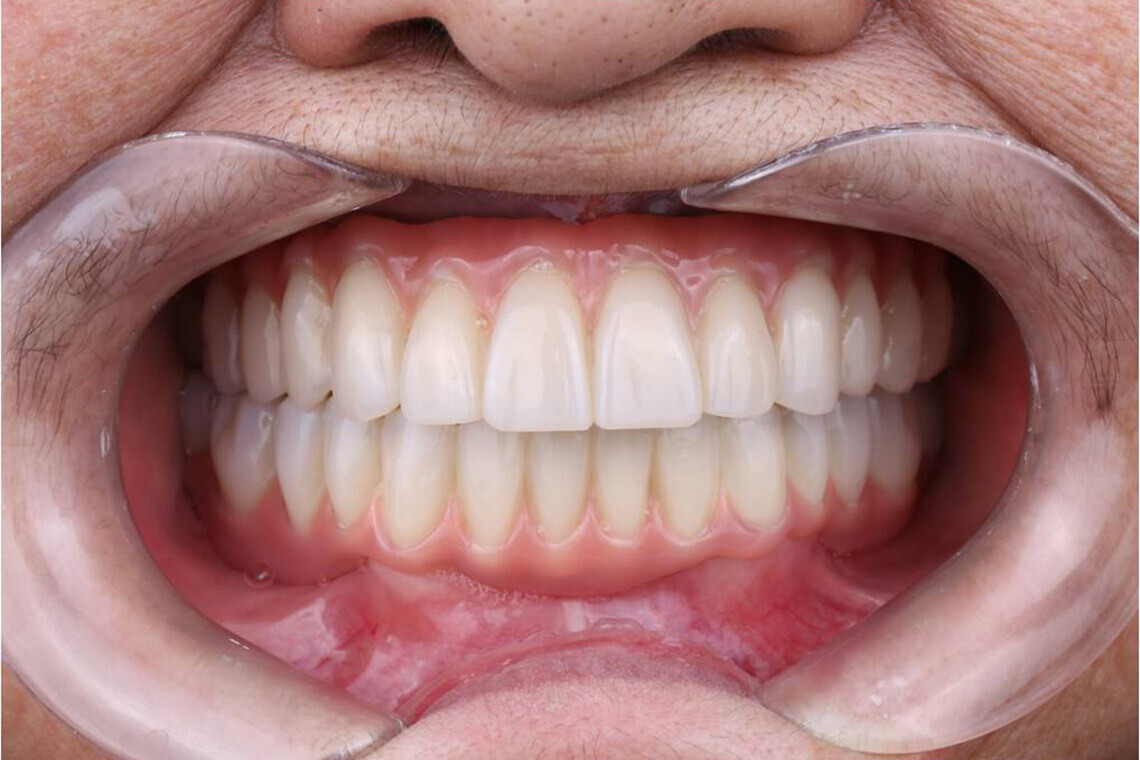

- Высокие эстетические свойства.